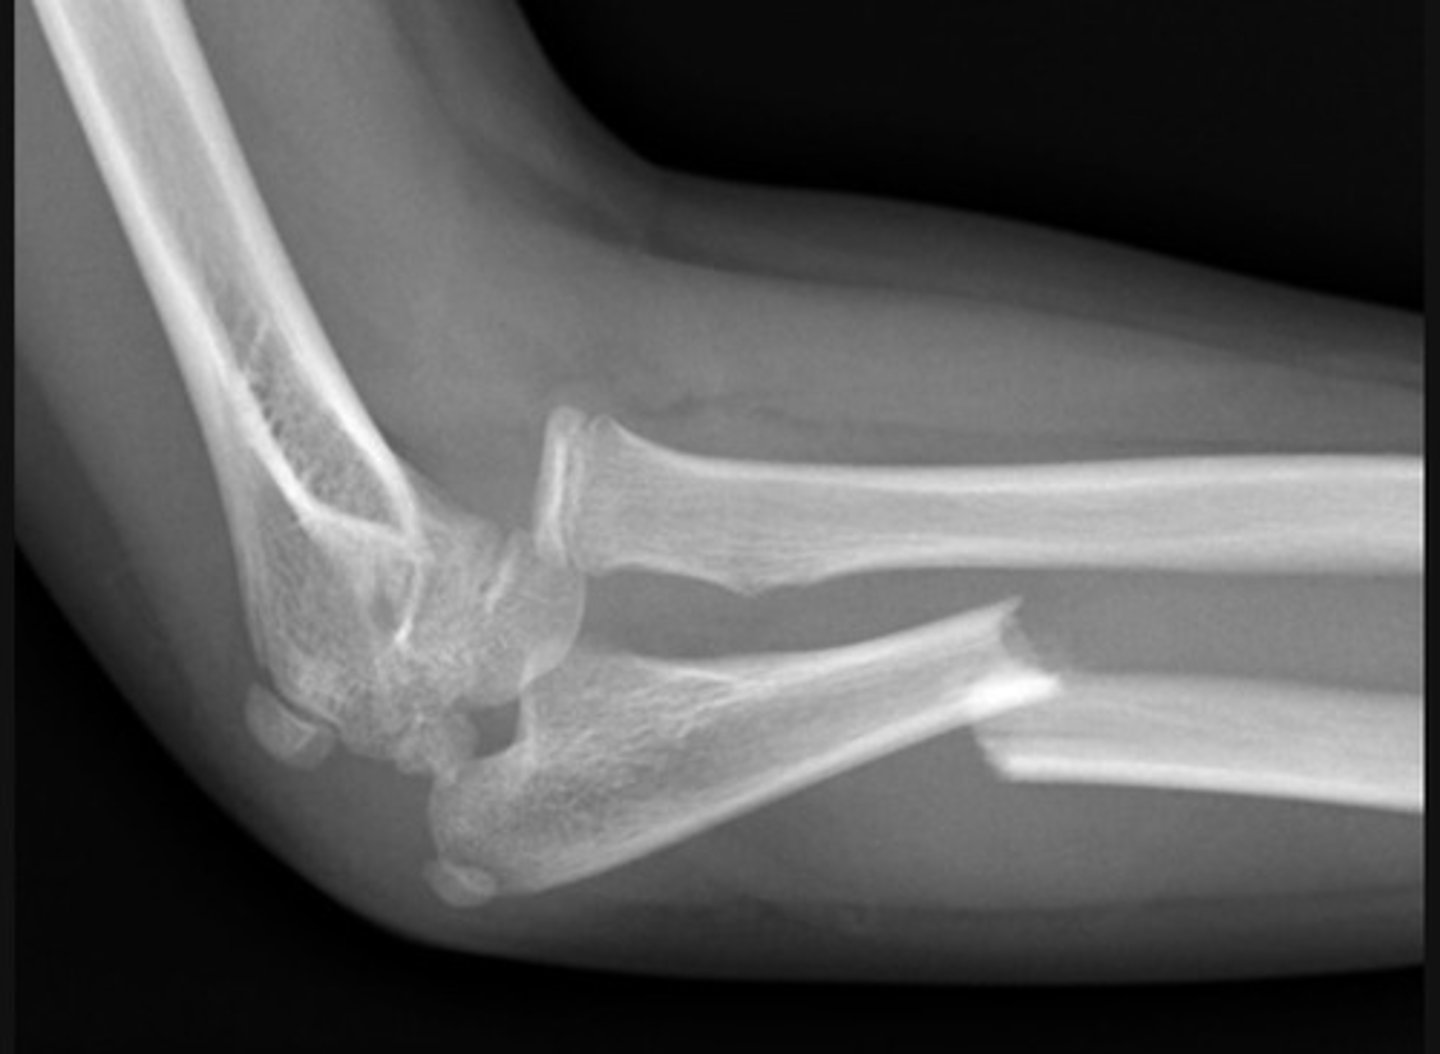

Monteggia fracture-dislocation - Lateral

a fracture of the ulnar shaft with dislocation of the radial head at the elbow

The radiocapitellar line should pass through the middle of the capitulum of the humerus